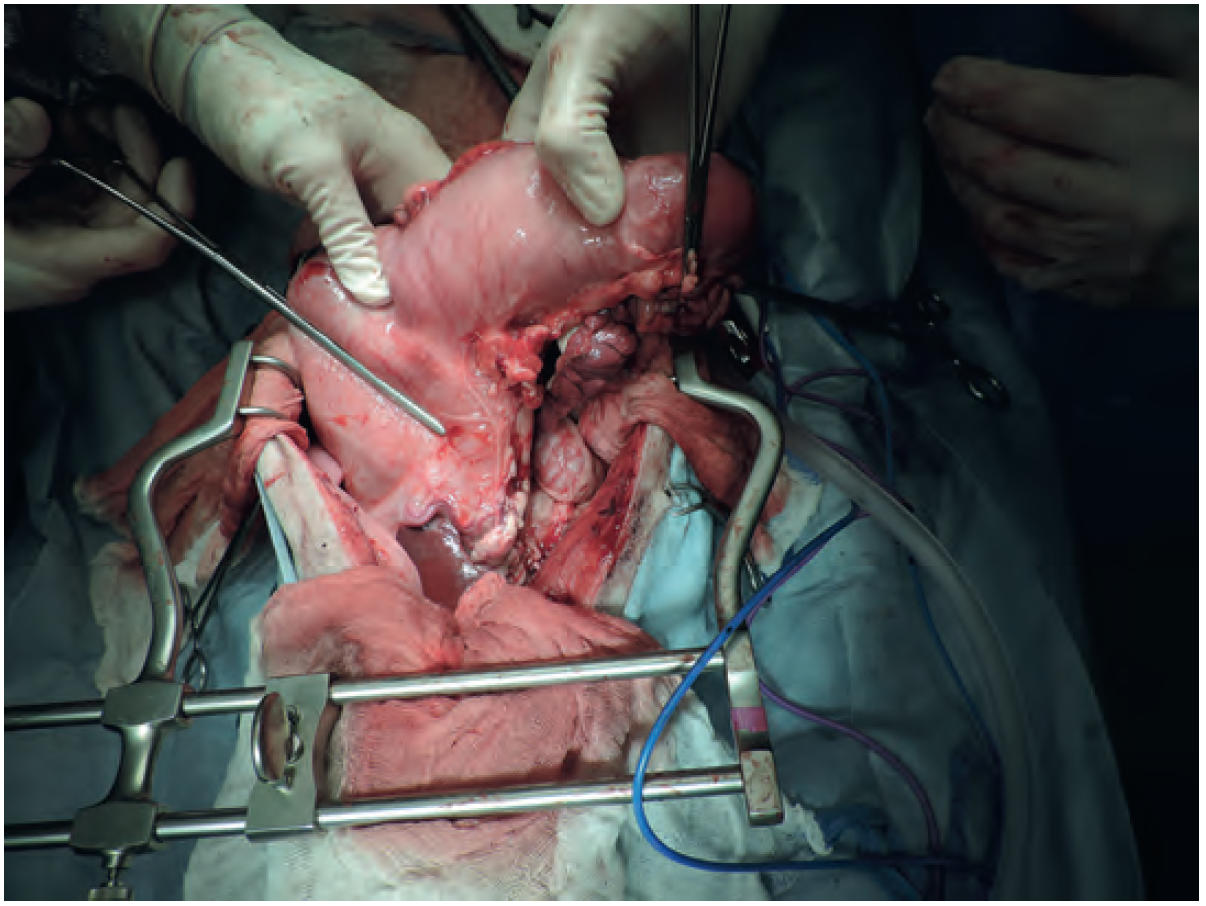

- 开腹手术活检是金标准,通常需要用于确认诊断(图2、3)。

图2. 图1中胃部肿块的术中视图。肿瘤沿胃小弯从幽门窦延伸至胃体,由外科医生的拇指勾勒出范围。Doyen钳代表胃切除的范围,而止血钳用于血管结扎。注意胰腺左侧部位的变色,该部位在手术中被切除。

图3. 图2中胃部肿块切除后的术后视图。该图像显示了胃十二指肠吻合术(下)和胆囊十二指肠吻合术(上)部位的切口线。Doyen钳放置在手术部位的远端,胆囊在图像的右上方可见。